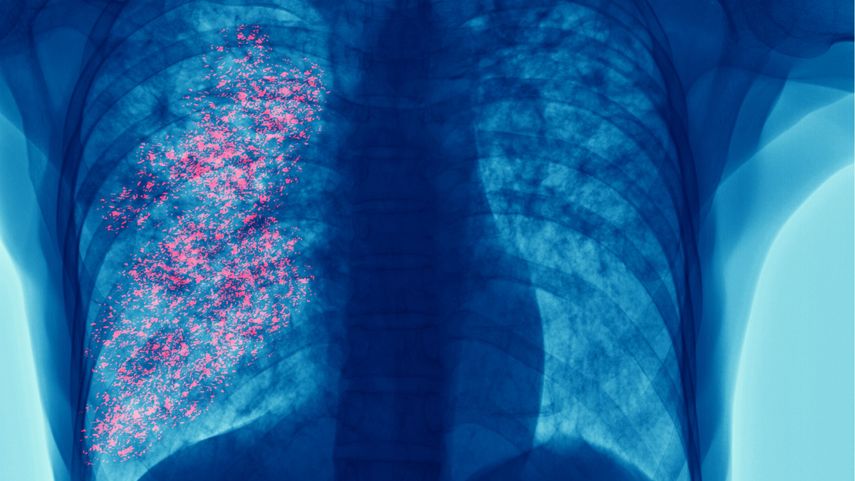

El cáncer de pulmón es responsable de 1.8 millones de muertes al año, más que cualquier otro tipo de cáncer. En Panamá, se registran 370 casos nuevos y más de 300 defunciones cada año, representando el 8.1% de los diagnósticos oncológicos.

El tabaquismo es el principal responsable del 64% de los casos y del 79% de las muertes. También influyen el humo de segunda mano, los vapeadores, la contaminación y el uso de leña para cocinar. Los síntomas tos persistente, falta de aire, dolor de pecho, cansancio y pérdida de peso suelen ignorarse o confundirse con problemas menores.

El abordaje del cáncer de pulmón debe incluir diagnóstico temprano, referencia oportuna y acceso a terapias efectivas como quimioterapia, radioterapia, cirugía e inmunoterapia. Las innovaciones en medicina de precisión y terapias dirigidas desarrolladas por AstraZeneca permiten atacar mutaciones específicas y mejorar el pronóstico.